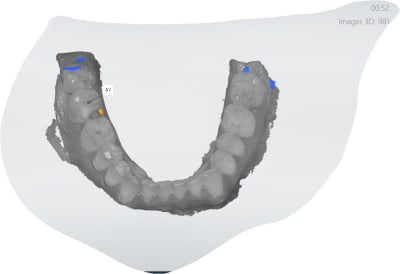

Oui des empreintes turbo. Préprep le temps que l'anesthésie de de 27 et 47 prennent pour les endos. Pour l'empreinte des préparations c'est 15 secondes. -))))